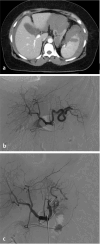

Methods: This is a retrospective study with Institutional Review Board approval. The medical records of 450 patients with BSI treated between January 2016 and December 2022 were reviewed. Seventy-two patients were treated with splenic artery embolization (SAE), met the study criteria, and were eligible for data analysis. Spleen injuries were graded in accordance with the American Association for the Surgery of Trauma Organ Injury Scale. Univariate data analysis was performed, with P < 0.05 considered statistically significant.

Results: The splenic salvage rate was 90.3% (n = 65/72). Baseline demographics were similar between the groups (P > 0.05). Distal embolization with Gelfoam® had similar rates of splenic salvage to proximal embolization with coils (90% vs. 94.1%, P > 0.05). There was no significant difference in the rate of splenic infarction between distal embolization with Gelfoam® (20%, 4/20) and proximal embolization with coils (17.6%, 3/17) (P > 0.05). There was no significant difference in procedure length (68 vs. 75.8 min) or splenic salvage rate (88.5% vs. 92.1%) between proximal and distal embolization (P > 0.05). There was no significant difference in procedure length (69.1 vs. 73.6 min) or splenic salvage rate (93.1% vs. 86.4%) between Gelfoam® and coil embolization (P > 0.05). Combined proximal and distal embolization was associated with a higher rate of splenic abscess formation (25%, 2/8) when compared with proximal (0%, 0/26) or distal (0%, 0/38) embolization alone (P = 0.0003). The rate of asymptomatic and symptomatic splenic infarction was significantly higher in patients embolized at combined proximal and distal locations (P = 0.04, P = 0.01).

Conclusion: The endovascular management of BSI is safe and effective. The overall splenic salvage rate was 90.3%. Distal embolization with Gelfoam® was not associated with higher rates of splenic infarction when compared with proximal embolization with coils. Combined proximal and distal embolization was associated with a higher incidence of splenic infarction and splenic abscess formation.